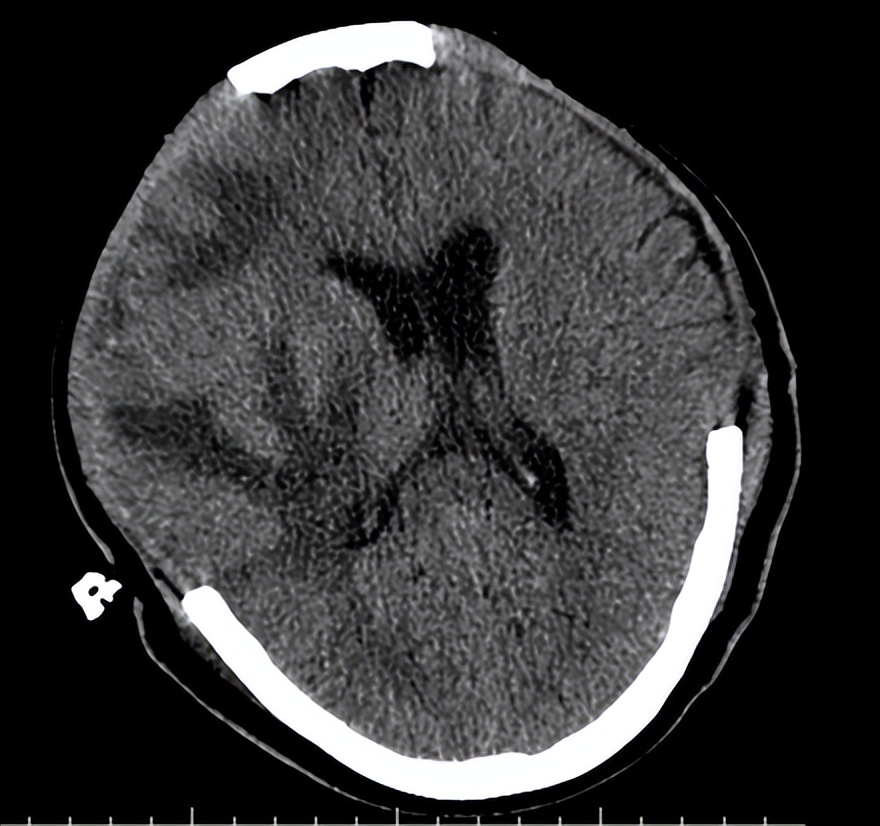

术后第三天,复查头颅CT(见下图)提示患者 脑水肿较前明显, 中线较前移位明显。目前正处在脑水肿高峰期,如果中线移位继续加重时,有必要 再次开颅 进行血肿清除。 病情危重 ,院方向患者家属交待病情,家属中有一位懂医的,都表示理解。

06-10(术后第三天复查头CT)

我被邀请查看了该患者。我先看了6月10日的头颅CT,又亲自检查了患者。

当时患者仍呈 昏迷状态 ,血压148/70mmHg,自主呼吸不规则,需有创呼吸机辅助通气,痰多,有明显痰鸣音。双侧瞳孔等大,约1.5mm,对光反射消失。脑干反射明显减弱。疼痛刺激右下肢回缩反应,左下肢无肢体回缩,双侧巴氏征阳性。

最近一次头颅CT,脑水肿明显,中线移位,双侧脑组织有继发性血肿。